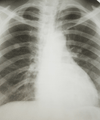

Poorer lung cancer patients in the developed world are significantly less likely to receive treatment than richer patients, researchers from Newcastle University have found.